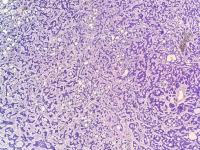

王功伟老师肾脏肿瘤系列讲座(十五):

王功伟

北京大学人民医院病理科